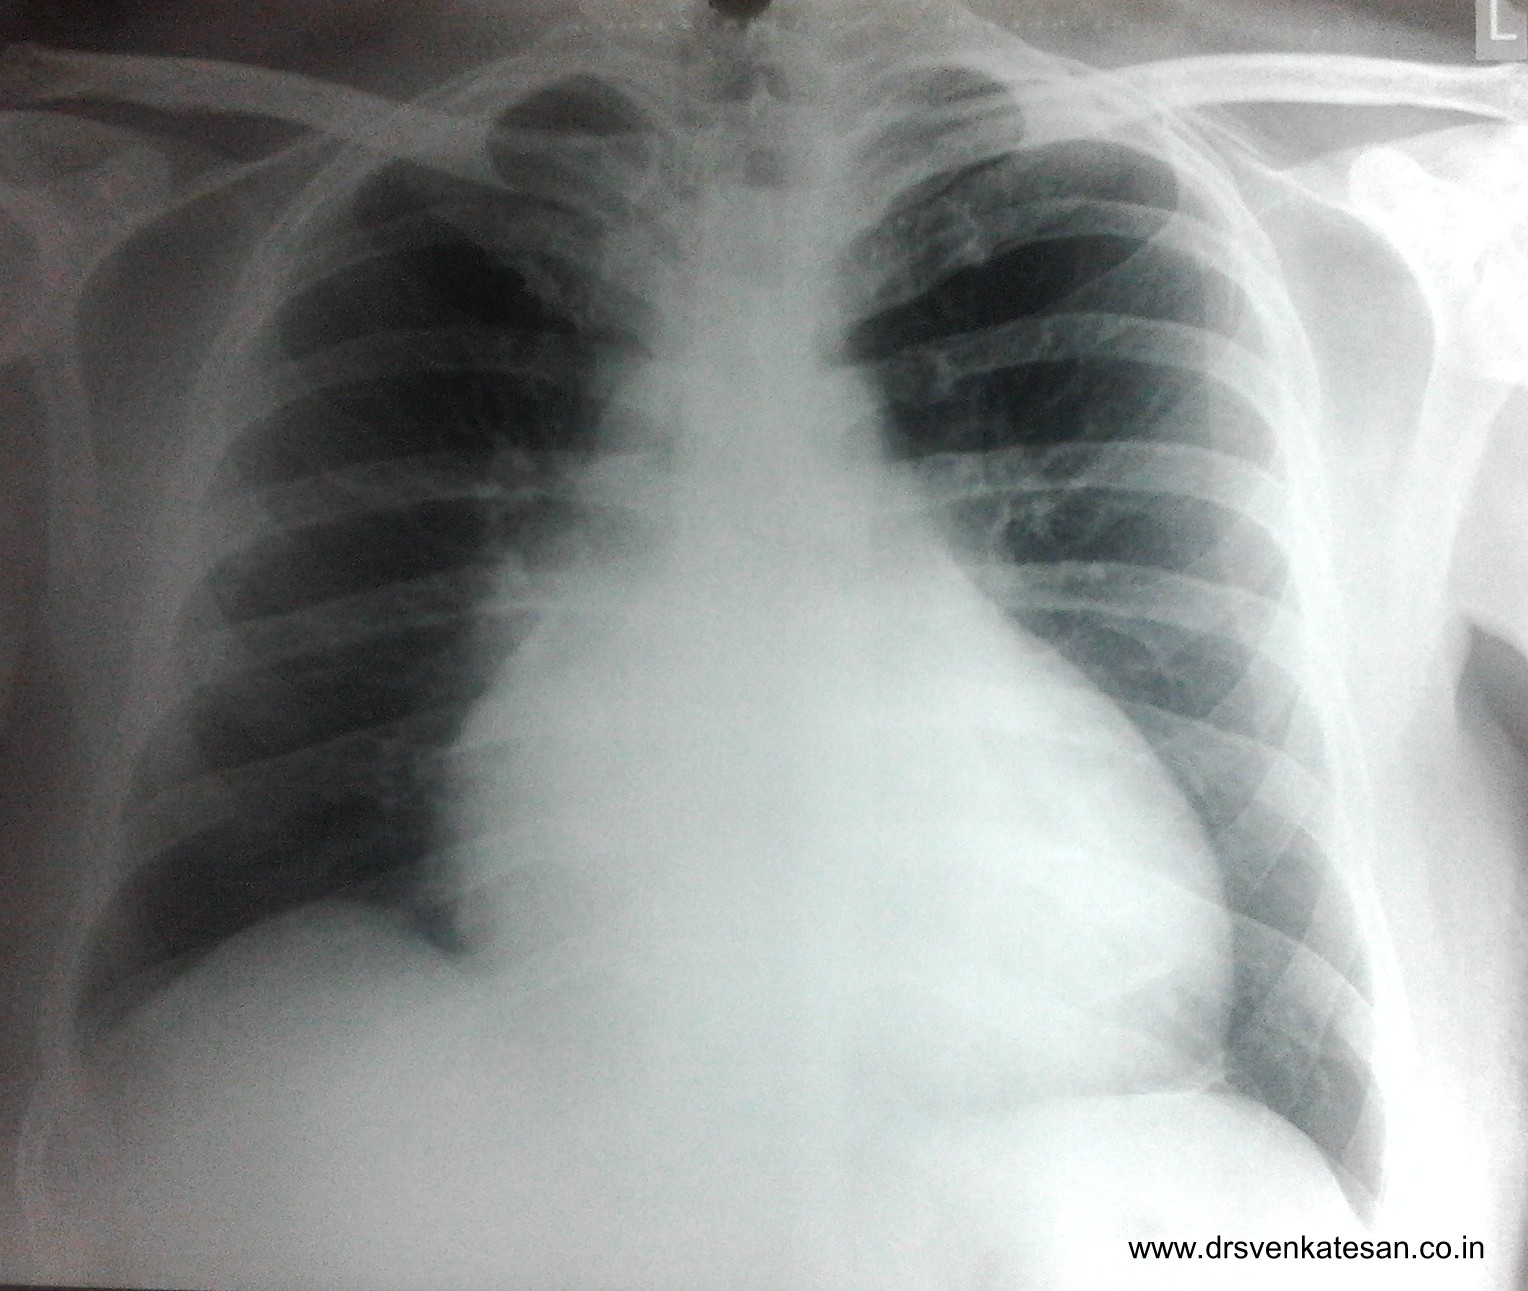

Here is a patient with class 3  dyspnea  who was referred  for echocardiography

X ray chest showing cardiomegaly

Moderate TR due to dilatation of tricuspid annulus.This patient had dilatation of all 4 chambers of the heart.LV EF was 24 %

Right ventricular dysfunction is major determinant of  clinical outcome in patients with dilated cardiomyopathy. The  myocardium of the  entire heart is now known to be a single sheet of muscle rolled into different chambers . So any primary disease of myocardium will involve the entire musculature . This is the reason  , all the  4 chambers of heart goes for dilatation in  primary cardiomyopathy . Of course there can be minor variations  due to differential hemodynamic impact.